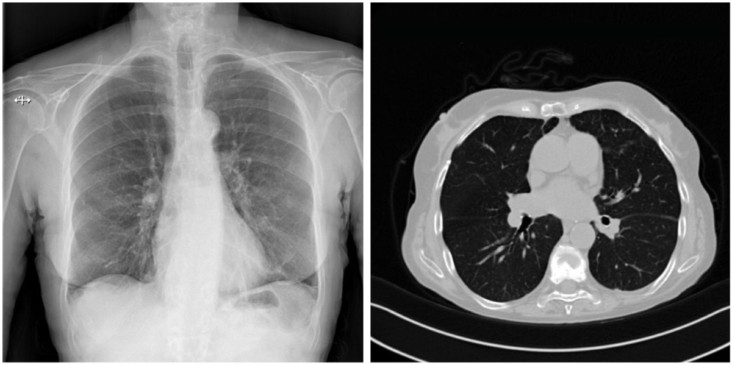

Read article: Transfer-learning models detect COVID-19 from lung CT images

A new deep-learning framework achieves up to 97% accuracy in detecting SARS-CoV-2 infection from patient lung scans